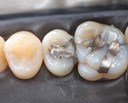

Alan Chinn #2 amalgam removal

Alan Chinn #2 prep

Kyle Chock #30 pre-op